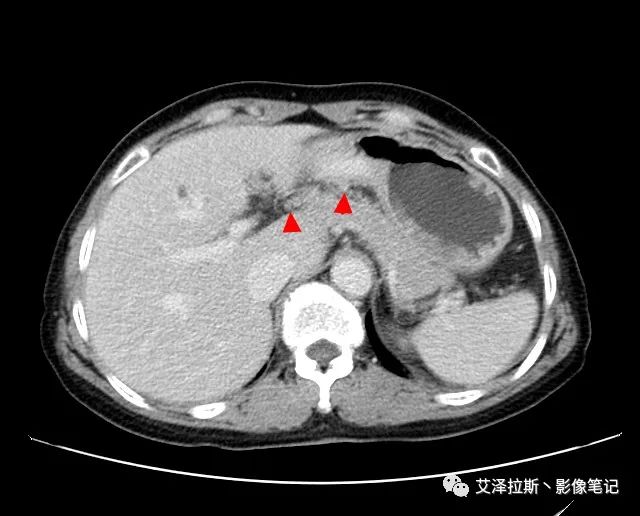

圖1 平掃+增強各期

【影像所見】 胃竇部狹窄,胃壁環形增厚,小彎側見一巨大潰瘍,周圍伴“環堤征”,漿膜面不完整,胃周脂肪見網格狀條索影,病灶與肝臟左葉、胰腺鉤突脂肪間隙消失,增強掃描病灶明顯強化。引流區內約15個區域淋巴結受累。

【診斷意見】 胃竇部胃癌(T4N3期) 該病例腫塊突破漿膜層,與肝臟左葉、胰腺鉤突分界不清,脂肪界面消失,定為T4期; 受累及的淋巴結為15個區域,定為N3; 有無遠處轉移尚不明確,所以M期暫時無法確定。